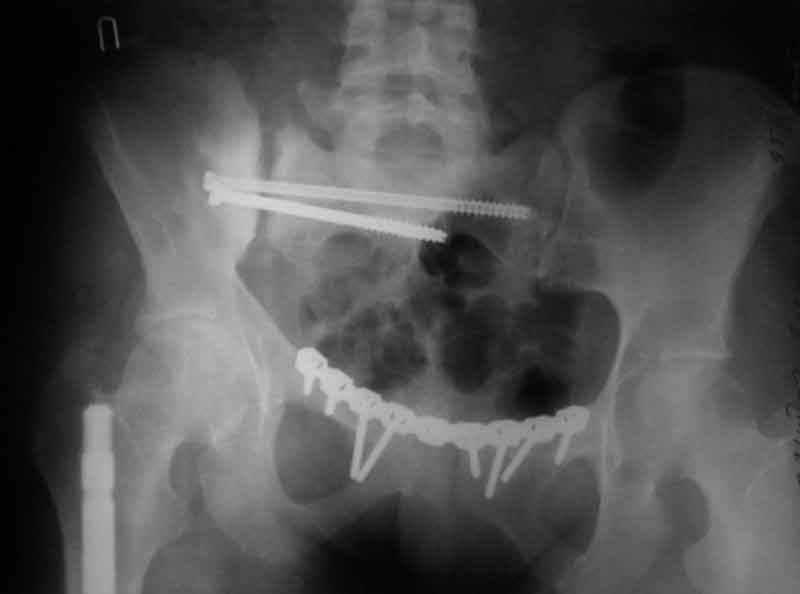

[Ortho] Застарелое повреждение таза

> прилагаю пример с такой же давностью травмы, репонировали аппаратом